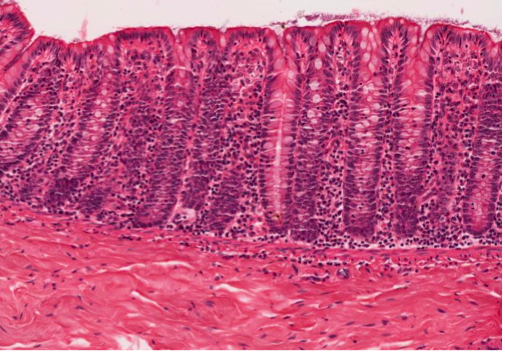

colon

Straight tubular glands (like test tubes in a rack). You don’t really find Paneth cells as a general feature. There’s a smooth surface epithelium